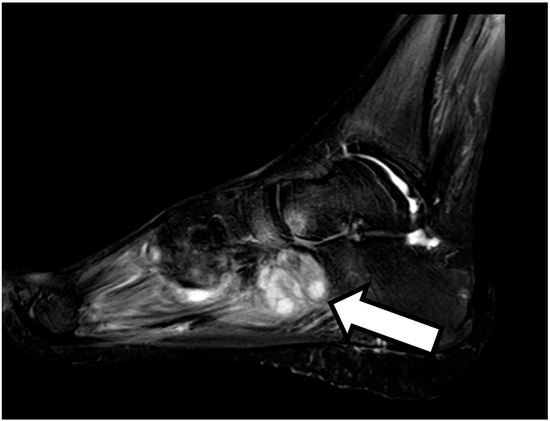

The Appearance of Osteomyelitis of the Foot and Disseminated Subcutaneous Abscesses During Treatment for Disseminated Tuberculosis Infection in an Immunocompetent Patient: Case Presentation of a Paradoxical Reaction and Literature Review

2. Case Presentation